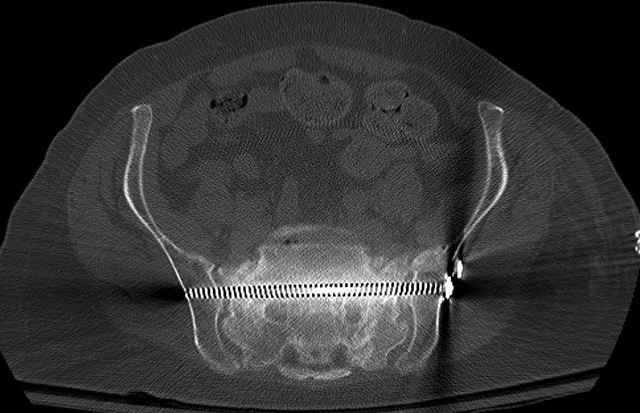

Here are a recent patient’s example slides...

Pelvic CT Scan - 3 Months After Fall

Sacral Injuries

Ramus Fractures

Percutaneous Fixation

(B) Ramus-Retrograde

2 TransIliac-TransSacral

Upper Segment

mlcr